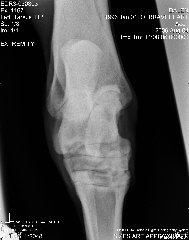

Left tarsus dp

Left tarsus DLPM

Aileen, carefully reviewing an extensive list of radiographs like you have above for any abnormality even with the original set of full sized radiographs could take up to an hour and an hour more to write about. Reviewing these tiny pictures would be of no value at all. While I don't mind looking at the occasional radiograph the above is beyond the scope of this site.

If you want a second opinion on these I strongly recommend you send them to a certified veterinary radiologist, like you find at a university veterinary school, they could tell you more than I would be able to.

Surgeon says mild to moderate djd in hocks and stifle. His stiffness is much much better, not overall anymore, so I do think the hock injections helped.